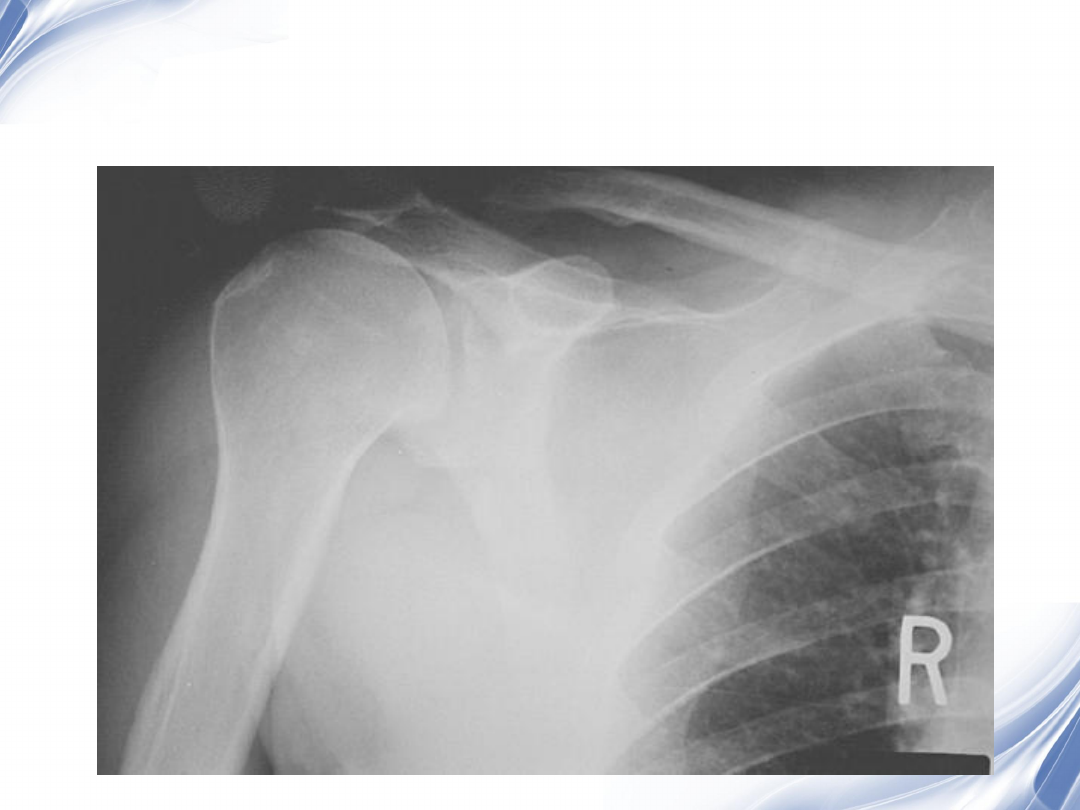

影像学

-X

线

正常肩关节

肩峰撞击

22

巨大肩袖损伤肩峰下间隙

<9mm

23